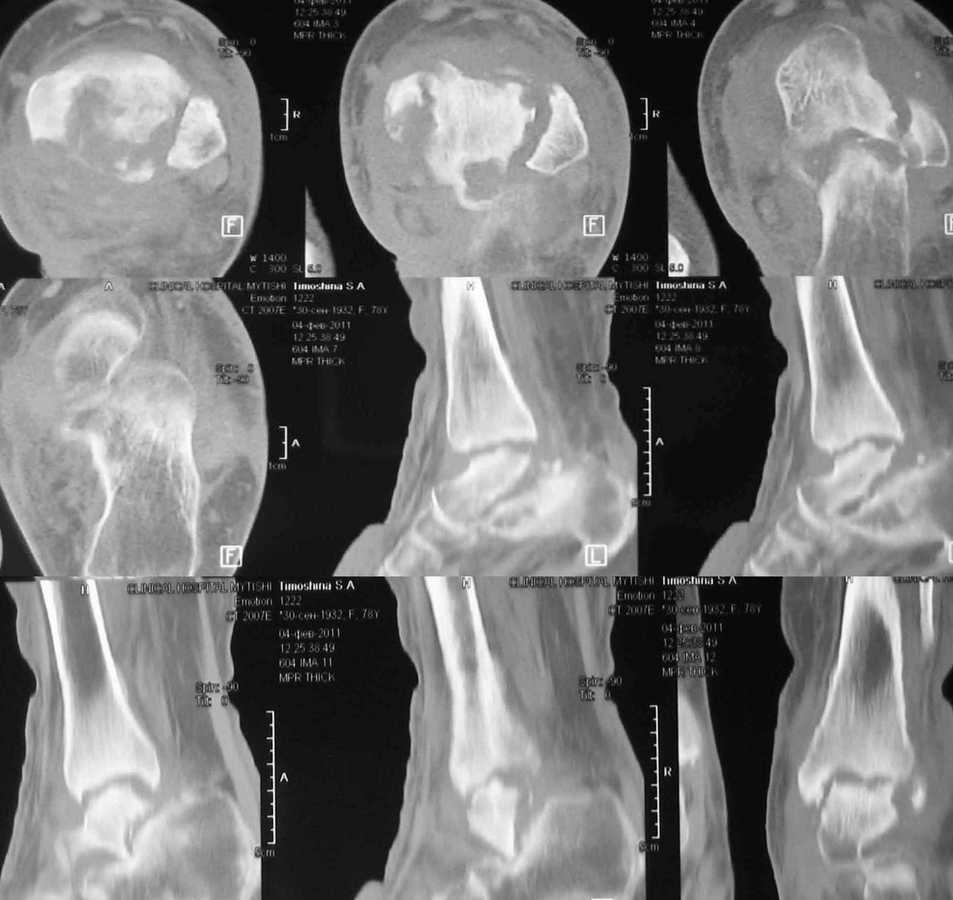

Женщина 78 лет. После инъекции дипроспана (несколько месяцев назад) развился артрит с некрозом тарана

Полгода назад в сустав дважды вводили дипроспан с целью лечения артроза. Спустя некоторое время появился отек, боль и пр. Три месяца назад дугообразным разрезом вскрыли абсцесс по задне-внутренней поверхности голеностпоного сустава. Теперь там свищ со скудным гнойным отделяемым.КТ и внешний вид на картинках.Хотелось бы услышать мнение коллег по тактике лечения.